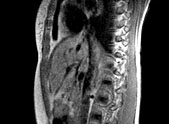

MRT des Bauchbereichs (Abdomendisgnostik)

Zur Untersuchung der Leber gibt es eine Vielzahl von Untersuchungsmethoden z.B. MRT (aber auch Ultraschall und CT). Aufgrund der in der Leber enthaltenen Strukturen und ihres unterschiedlichen Gehalts an Wasser, Fett, Zellen, Bindegewebe und Blut - also wasserstoffhaltigen Weichgewebsanteilen - ist die MRT hier die Diagnosemethode der Wahl.

Durch Kontrastmittel können morphologische Veränderungen, Durchblutung (Perfusion) und Leberfunktion eindrucksvoll dargestellt und sicher bewertet werden.

Lebertumor

Nierentumor